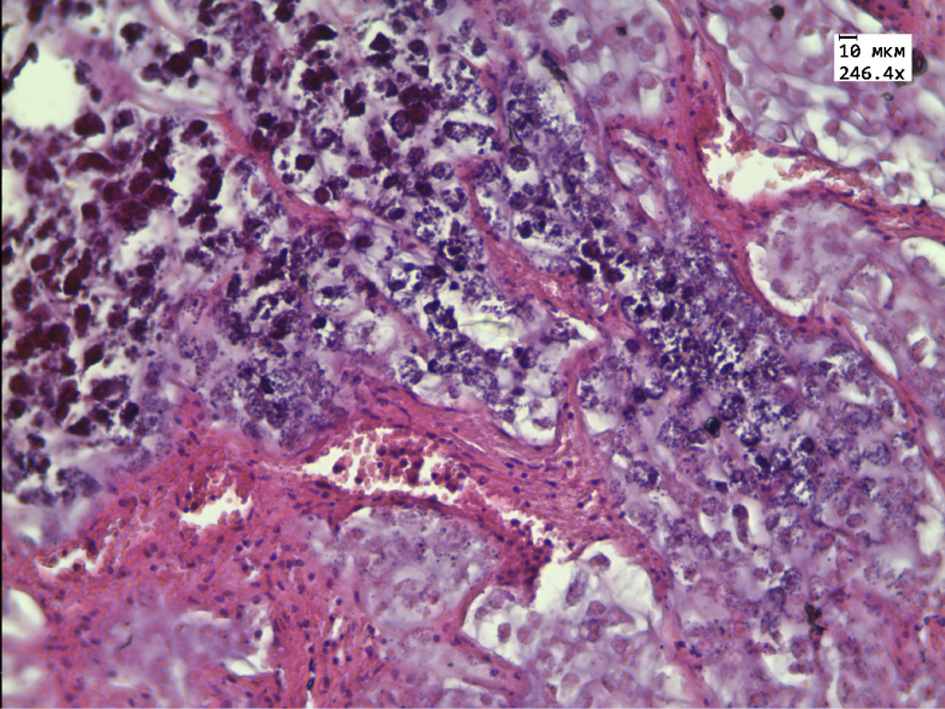

During the morphological and morphometric study of the tumor tissue in the rats group receiving alcoholic thyme extract, attention was paid to the pronounced pathomorphosis mainly in the central parts of the tumor. A large number of “shadow cells”, a decrease in the size of tumor cells, and extensive zones of necrosis were noted. The intact tumor cells are represented by small rounded cells with rounded or bean shaped nuclei with single small vacuoles containing mucus. The tumor cells are located in cells formed by thickened connective tissue partitions with a large number of thin-walled blood vessels. Connective tissue fibers are infiltrated by lymphocytes. Mitosis was determined only in one case of observation (Fig. 2).

Figure 2 – Histological structure of the transplanted hepatic cancer in the group receiving alcohol extract of Thymus marschallianus Willd.

Note: dystrophic and necrotic changes in tumor cells, “shadow cells” (black arrow), thickening of connective tissue partitions (white arrow). Stained with hematoxylin and eosin. Magnification 246.4×.